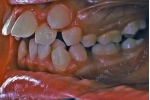

治療前後の比較